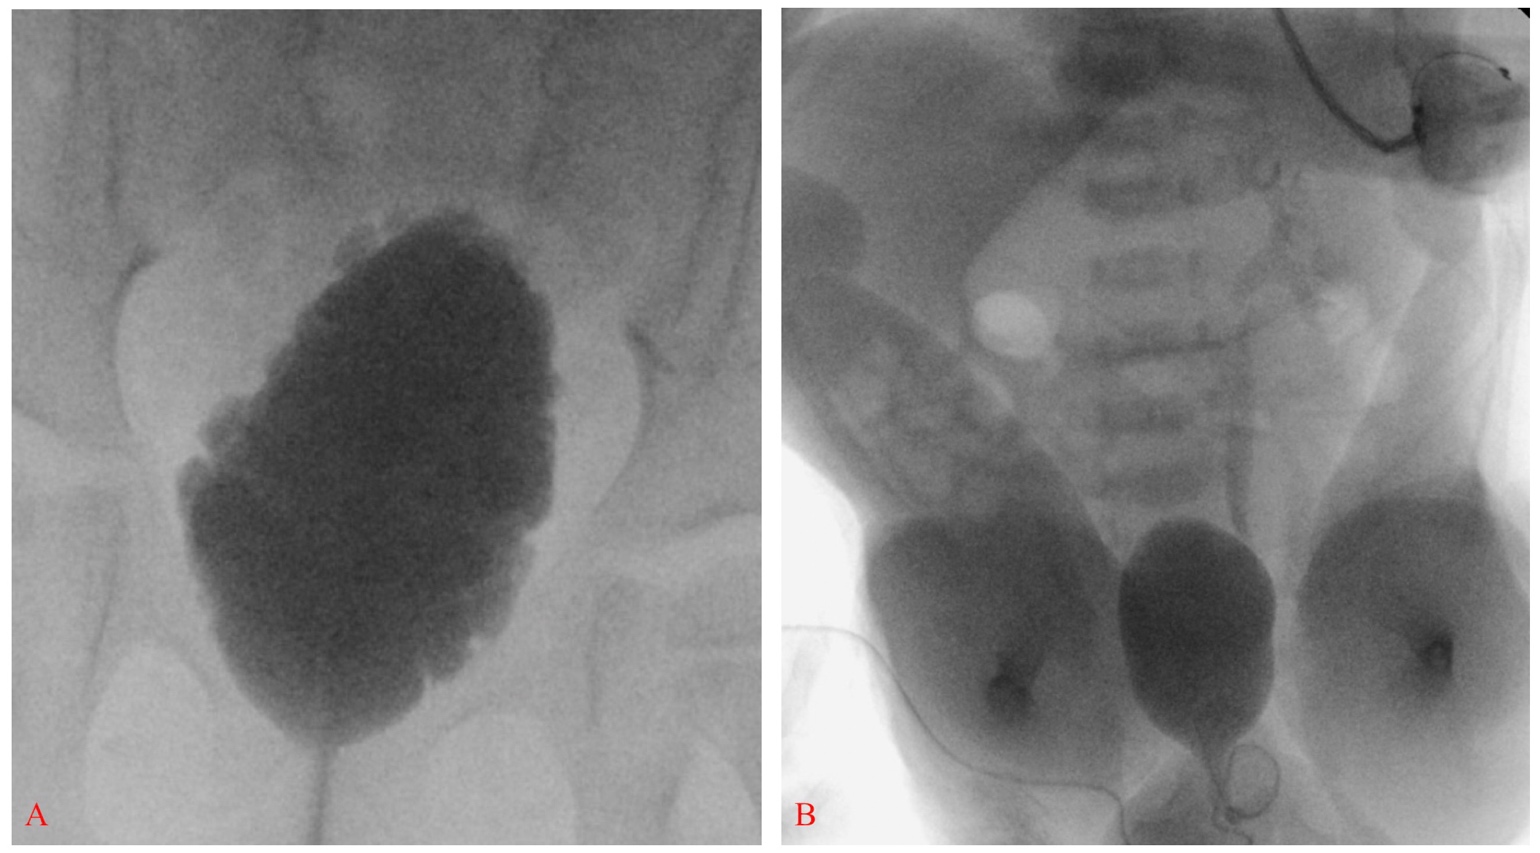

From radiopaedia.org

Neurogenic bladder Image How Long Does Neurogenic Bladder Last Neurogenic bladder is caused by damage to the nerves that allow you to control the timing of urination. Learn more about the causes, symptoms,. Neurogenic bladder is a condition caused by the nerves along the pathway between the bladder and the brain not working properly. If your brain or nervous system is damaged, it can affect how your bladder works.. How Long Does Neurogenic Bladder Last.